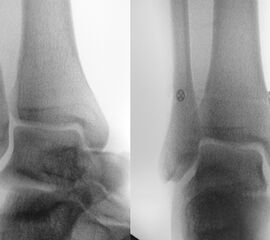

Röntgenaufnahmen dienen primär dem Ausschluss einer knöchernen Verletzung. Die Beurteilung der Geometrie der Malleolengabel kann einen ersten Hinweis auf eine Syndesmosenverletzung liefern. Die notwendigen Röntgenaufnahmen umfassen das Sprunggelenk anterior-posterior, lateral und in 20° Innenrotation (Mortise view). Zur Beurteilung der Syndesmose sind verschieden Parameter in der Mortise view beschrieben. Zu diesen zählen der tibiofibulare Clearspace, der mediale Clearspace, sowie die Überlappung der distalen Fibula und Tibia im Bereich der Incisura (Abbildung 2). Der Tibiofibulare Clearspace wird als verlässlichster Indikator für eine Syndesmosenverletzung gesehen, da er nicht signifikant von der tibialen Rotation beeinflusst wird 32. Er wird 1 cm proximal des Tibiaplafonds gemessen und sollte weniger als 6mm betragen 33. Jede Messung, die diesen Wert übersteigt, stellt einen Hinweis für eine Syndesmosenverletzung dar. Eine tibiofibulare Überlappung von 6 mm oder mehr in der AP Aufnahme, sowie mehr als 1 mm in der Mortise View Aufnahme gelten als physiologisch 33. Der mediale Clearspace sollte nicht mehr als 4 mm betragen 34.

Abbildung 3 zeigt ein Sprunggelenk nach Syndesmosenverletzung mit einem erweiterten Tibiofibularen Clearspace.